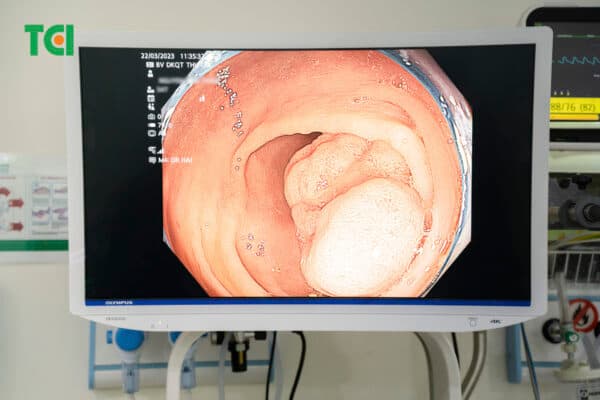

Polyp đại tràng nghịch sản thường có đặc điểm chung là kích thước lớn, bề mặt sung huyết, sần sùi, chia múi. Và từ đó, bác sĩ sẽ đánh giá mức độ nghịch sản của polyp theo 3 cấp độ:

Hình ảnh polyp đại tràng kích thước lớn chiếm trọn chu vi lòng đại tràng.